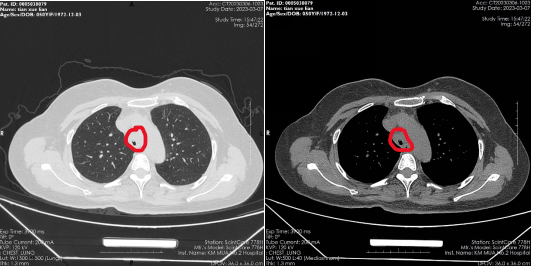

患者,女,50岁,因“外伤后呼吸困难2月”来到av线上 全科医学科治疗。患者2月前因外伤致气管撕裂,在当地医院行气管修补术,术后出现进行性加重呼吸困难。患者来到我院住院后,稍微活动就会感到气促,已不能活动,肺功能显示重度阻塞性肺通气功能障碍,胸部CT显示气管下段重度狭窄,支气管镜检查显示气管下段距隆突2cm处重度瘢痕狭窄,最窄处仅4mm,随时都会发生窒息甚至猝死,手术迫在眉睫!

气管下段狭窄治疗前

气管下段狭窄激光治疗+Y型硅酮支架植入后